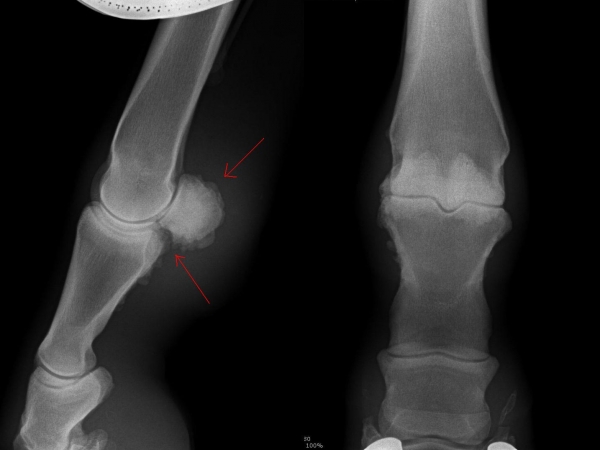

Čip ve spěnkovém kloubu na pánevní končetině

Ankylóza spěnkovýho kloubu

rentgenologické vyšetření

Fragment na spěnkové kosti